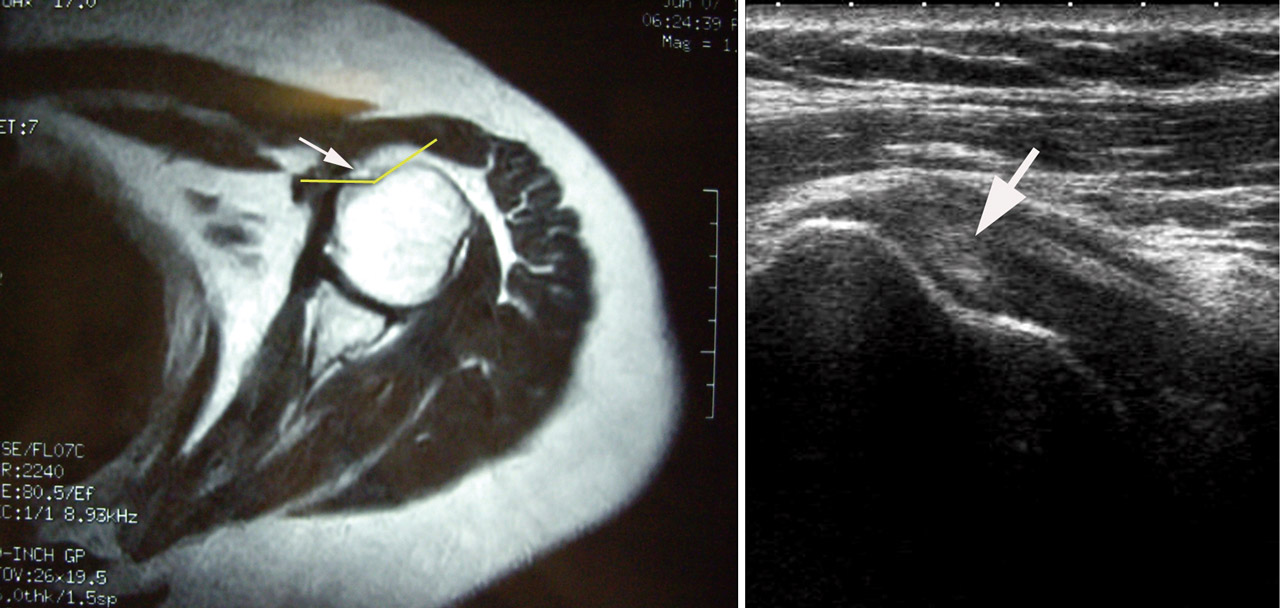

Dada la mala respuesta al tratamiento médico, se decidió realizar una descompresión subacromial artroscópica. En la exploración intraarticular se objetivó la ausencia del TPLB (Figura 1) con un labrum sin muestra de rotura actual o antigua. Se realizó una bursectomía artroscópica con vaporizador y acromioplastia con motor artroscópico. El postoperatorio trascurrió sin incidencias, presentando una recuperación clínica y funcional completa. Ante el hallazgo casual de la agenesia del músculo bíceps braquial, se revisaron las imágenes preoperatorias de RM, confirmándose la ausencia del tendón en la corredera bicipital, la cual se observó hipoplásica (Figura 2). Se realizó un estudio ecográfico contralateral donde también se objetivó que la agenesia bicipital era bilateral y una corredera hipoplásica (Figura 2).

Es necesario encontrar herramientas clínicas y pruebas imagen que nos ayuden en el diagnóstico diferencial entre lesión o agenesia del TPLB. Los test de O’Brien y Speed no son buenos para diagnosticar lesión aislada del tendón bicipital y suelen ser positivos cuando se añaden alteraciones del manguito. La ausencia del signo de Popeye y la falta de dolor a la palpación de la corredera bicipital son signos constantes en todos los estudios(1)(2). En la ecografía y la RM, los signos claves son falta de retracción del vientre muscular del bíceps, hipoplasia del surco bicipital(1)(2) e hipertrofia del ligamento semicircular del húmero(4). En nuestro caso, se trató de un hallazgo artroscópico casual, sin ser objetivado en la RM preoperatoria, que se confirmó posteriormente ante la del TPLB y una corredera bicipital hipoplásica. El estudio ecográfico del hombro contralateral confirmó que se trataba de una agenesia bilateral.